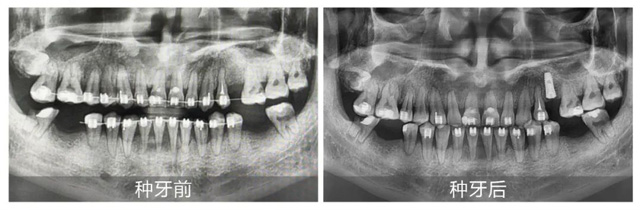

劉先生術前術后全景片對比